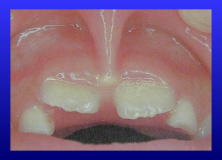

また、乳歯を磨くときには小さ目の歯ブラシをお使いと思いますが、上顎前歯の正中には小帯があるので痛がりませんか?

そんなときには前歯だけワンタフトブラシで磨いてあげましょう。

小帯を傷つけることなく、やさしい磨き心地でお子さんもきっと喜びますよ。